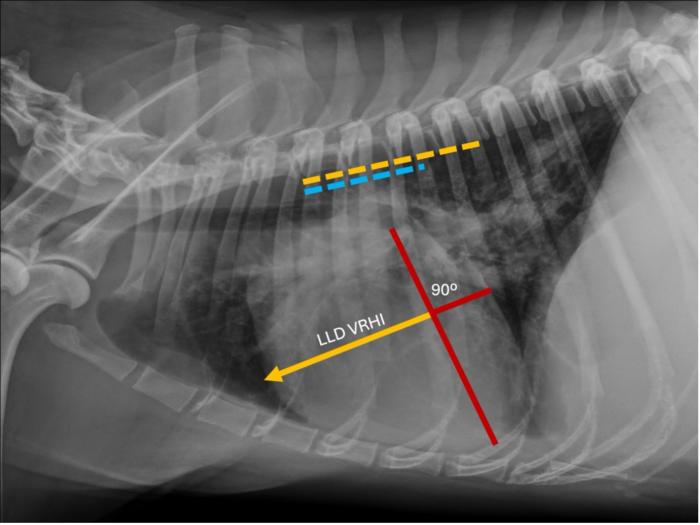

La determinación del VRHi se basó en el protocolo descrito por Puccinelli y colaboradores(2024). En la proyección LLD, el eje largo y el eje corto máximo de la silueta cardíaca se identificaron como se describió previamente para la escala cardíaco vertebral o índice de Buchanan (Buchanan & Bücheler, 1995). En el eje corto, se midió la distancia desde el margen craneal de la silueta cardíaca hasta la línea de intercepción del eje largo. Posteriormente, la misma línea se colocó sobre las vértebras torácicas comenzando en el borde craneal de la cuarta vértebra torácica, y se estimó el número de cuerpos vertebrales (CV). En la vista VD, el eje longitudinal torácico se trazó como una línea superpuesta a la columna vertebral. En el eje transversal, se calculó la distancia desde el margen derecho de la silueta cardíaca hasta el eje longitudinal torácico y se midió contra las vértebras torácicas en las vistas laterales, como se describió anteriormente (Figura 1 y 2).

Representación de la determinación del índice cardíaco vertebral derecho (VRHi) en proyección latero-lateral derecha (LLD) en un perro parasitado por Dirofilaria immitis y que sufría de hipertensión pulmonar. Valor de 3,9 cuerpos vertebrales al trasladar la determinación sobre las vértebras torácicas comenzando en el borde craneal de la cuarta vértebra torácica (línea de color naranja).